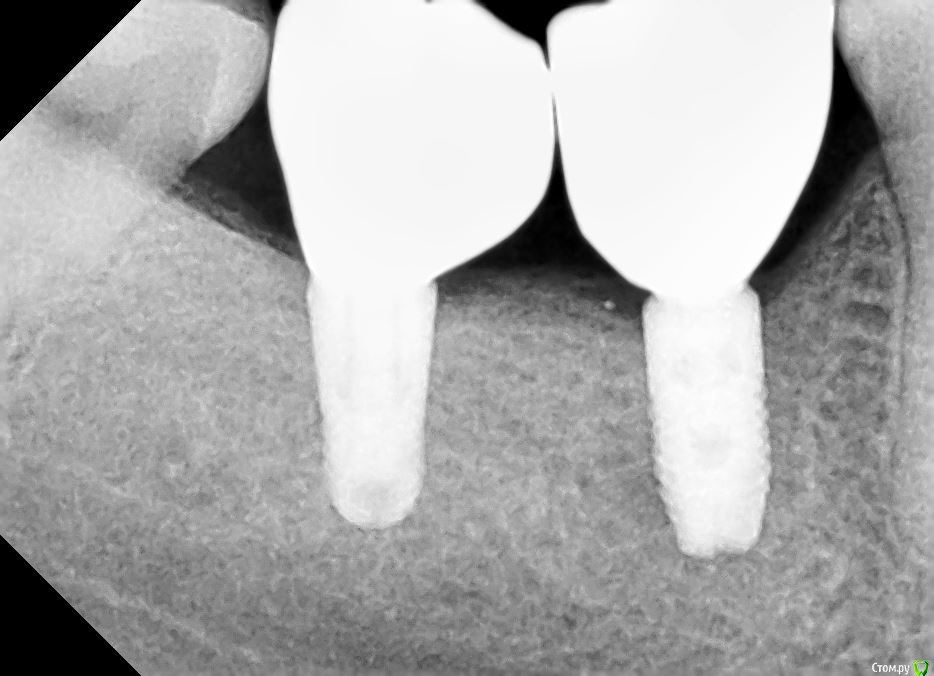

kramer Опубликовано 8 января, 2021 Поделиться Опубликовано 8 января, 2021 Нужны прицельные снимки с установленными коронками Ссылка на комментарий

Diana1974 Опубликовано 9 января, 2021 Автор Поделиться Опубликовано 9 января, 2021 Нужны прицельные снимки с установленными коронкамиПрикладываю Ссылка на комментарий

kramer Опубликовано 9 января, 2021 Поделиться Опубликовано 9 января, 2021 еда очень сильно набивается Где именно, уточните вызывает сильное давление и боль, жесткая еда и холод вызывают пульсацию Больше возле дальнего имплантата или ближнего? Ссылка на комментарий

Diana1974 Опубликовано 9 января, 2021 Автор Поделиться Опубликовано 9 января, 2021 Где именно, уточните Больше возле дальнего имплантата или ближнего? Больше всего застревает со стороны языка в промежутке между коронками, туда еда попадает так, что очень сложно достать без промывки ирригатором и нити, и соответственно находясь вне дома еда очень здорово раздражает десну (может это нормально, но я думала, что можно будет полноценно всё есть не зная боли).По поводу боли не могу определенно сказать, что она исходит от конкретной коронки, но она совершенно четко присутствует вне приемов пищи. Ссылка на комментарий